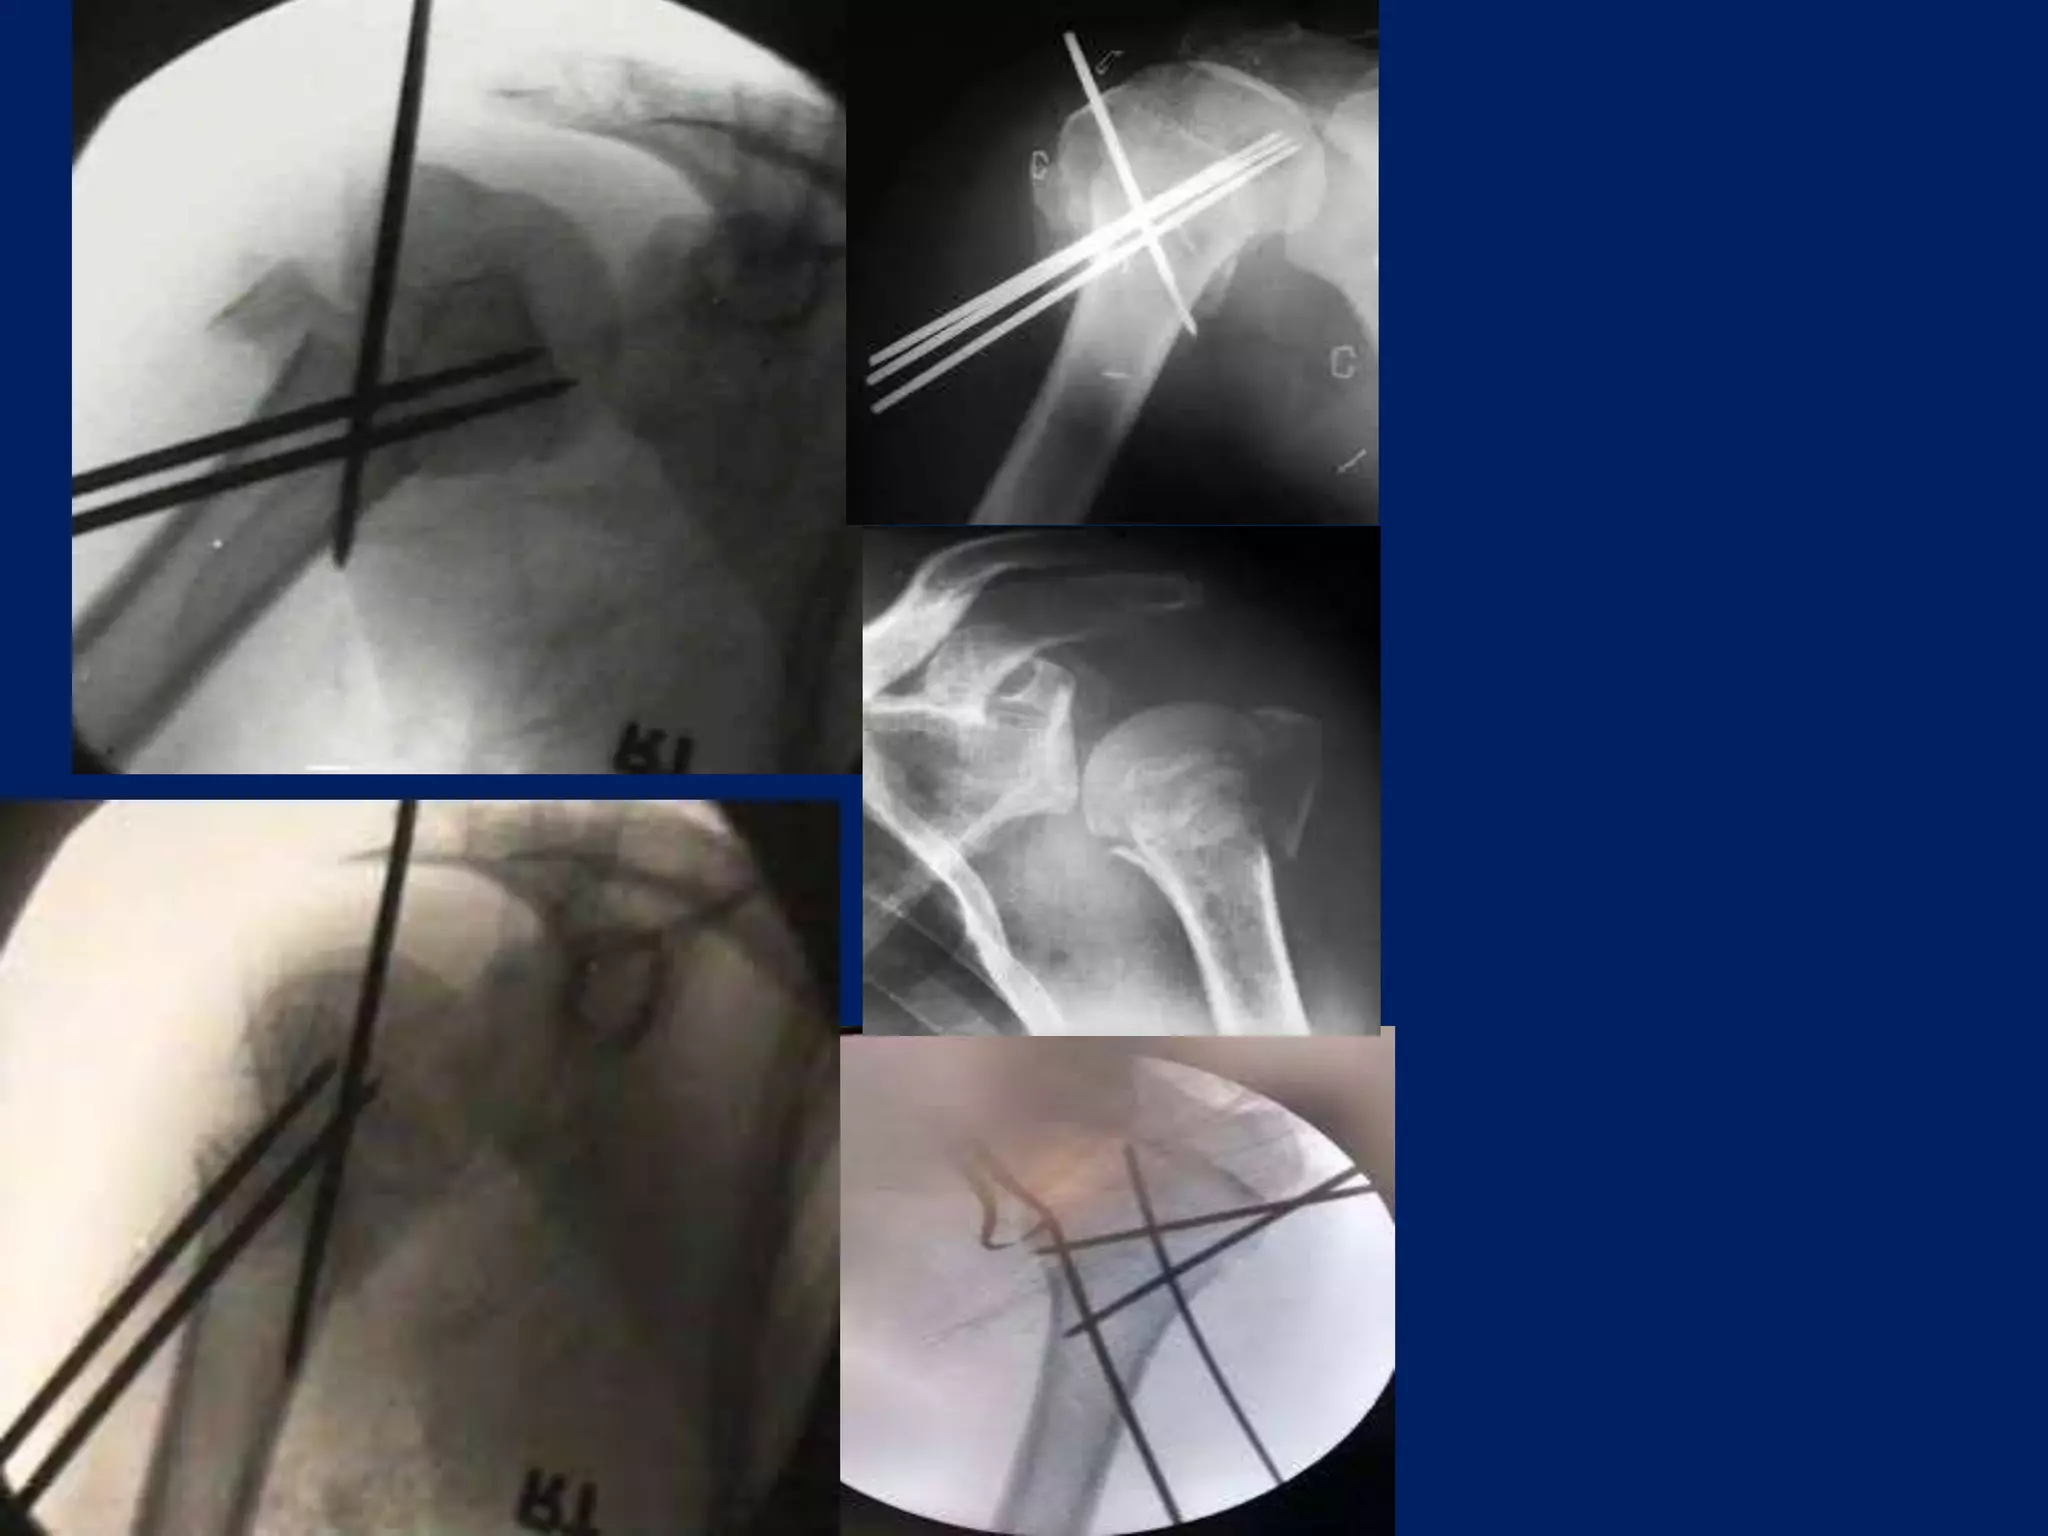

Operative contd... • 2.5mmSchanz pins/ K wire at humeral head at 300 to each other in horizontal plane. • 1st: In true lateral/ coronal plane 2nd: just lateral to bicipital groove 3rd: 300 posterior to 1st one.

A displacement ofGreater tuberosity superiorly may cause Impingement. A displacement posteriorly can cause External rotation is blocked.

• Next 2.5mmpin inserted in coronal plane in line with 1st pin, approximately 4cm or 3 finger/ below the 1st pin in upper third of Humerus. • 3rd pin placed 2cm below the above pin laterally. • Wires are placed from lateral cortex to medial cortex into the head upto the subchondral area

Operative contd... • Nowthe wires are joined through Link joints of JESS and a curved rod.

• A wirecan be placed from the head to bring down the head as near to the shaft.